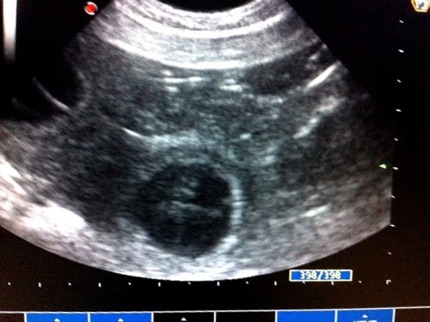

Berry olizuje mamku Cathy 13.5.2014 - 28.deň - sono - gravidita potvrdená